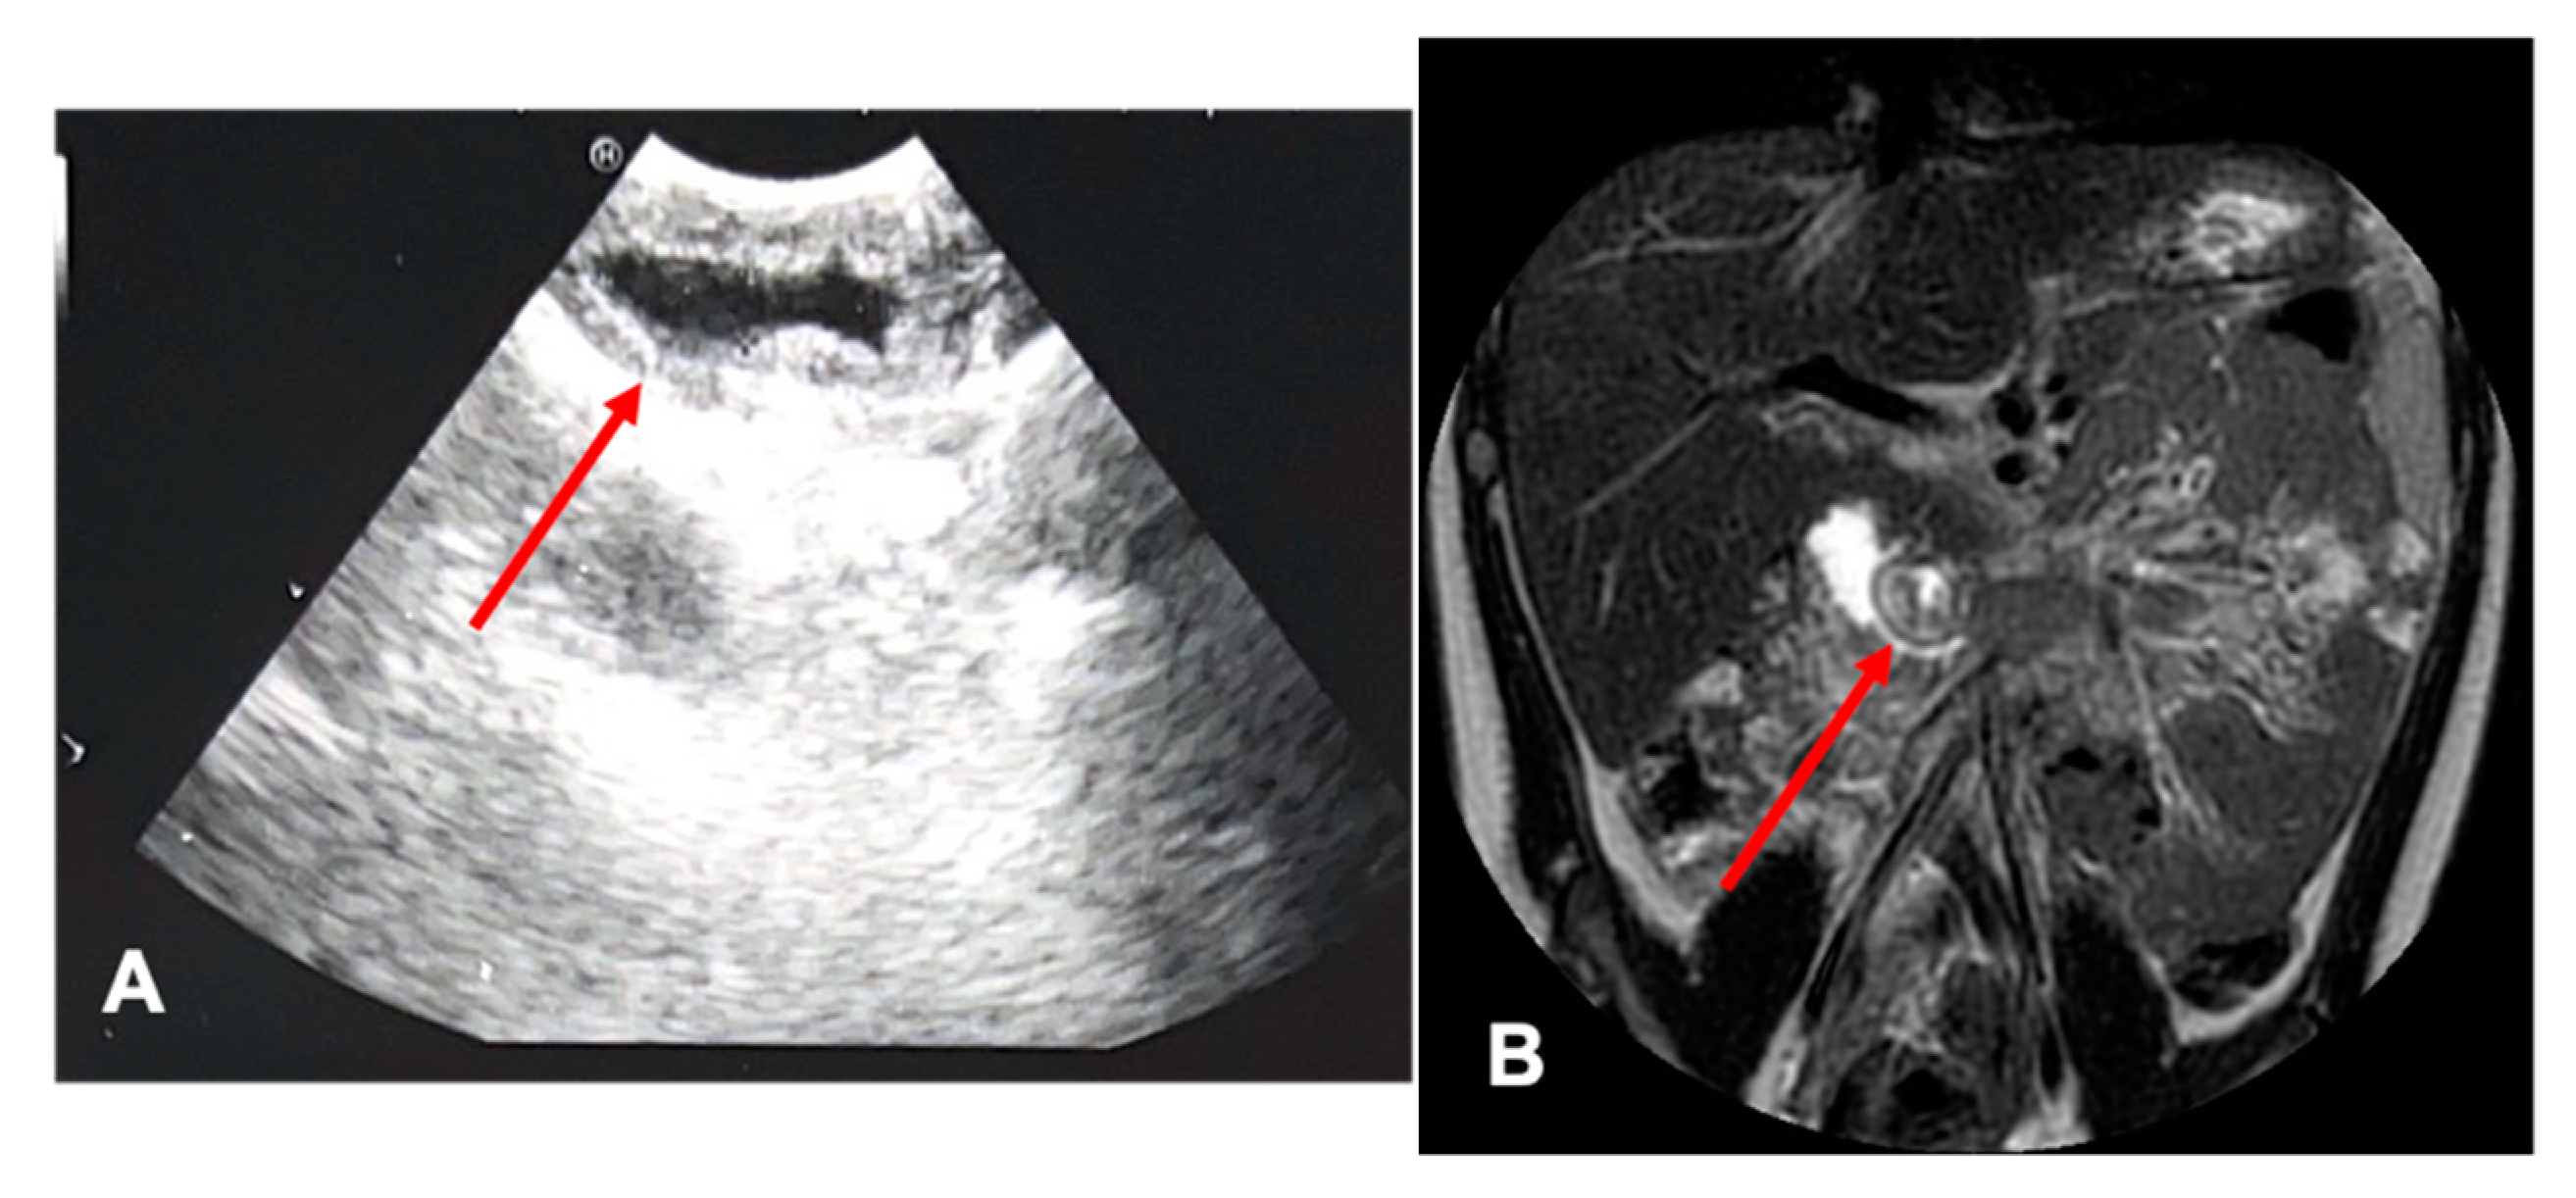

| Patients age, weight | Female 192 months 60 kg | Male 55 months 14 kg | Male 120 months 27 kg | Male 8 months 9 kg |

| Symptoms | Acute pancreatitis, pain in right hypochondrium | Icterus, pancreatitis | Chronic pancreatitis with choletithiasis, genetic-based | No |

| Diagnosis (prenatal evaluation yes/no) | Cholelithiasis and choledocholithiasis in duodenal atresia (duodeno-jejuno anastomosis at birth) and pancreas divisum (yes) | Choledochal cyst (Todani I) and choledocholitiasis (no) | Mutation of the gene PRSS1, Cholelitiasis, pancreatic duct duplication (no) | Gallbladder duplication Annular pancreas Duodenal duplication (yes) |

| Radiological investigations | US, MR, CT Scan, VR HMD | US, Cholangio MR | US, X-ray, Cholangio MR, CT, VR HMD | US, Cholangio MR, CT |

| Endoscopic instrumentation | EG-3870UTK Linear-Array Ultrasound Gastroscope | EBUS + Duodenoscope | Duodenoscope, EG-3870UTK Linear-Array Ultrasound Gastroscope | EBUS |

| Management | MIS (laparoscopic cholecisectomy) with LCBDE | 1. ERCP + sphincterotomy + stone removal 2. Open surgery: choledochal cyst removal and Roux-en-Y bilio-digestive anastomosis | 1. EUS + ERCP + stent placement + sphincterotomy + DASE; MIS (laparoscopic cholecystectomy) with LCBDE 2. ERCP and pancreatic stent replacement | MIS (laparoscopic cholecystectomies) with attempted LCBDE (failure for fibrosis) |

| Endoscopic Advantages/Limitations | Anatomical definition ERCP technically impossible for difficulties in reaching the papilla | Diagnostic and therapeutic procedures | Effective biliopancreatic drainage permitted postponed cholecystectomy and pancreatic preservation | Anatomical definition |